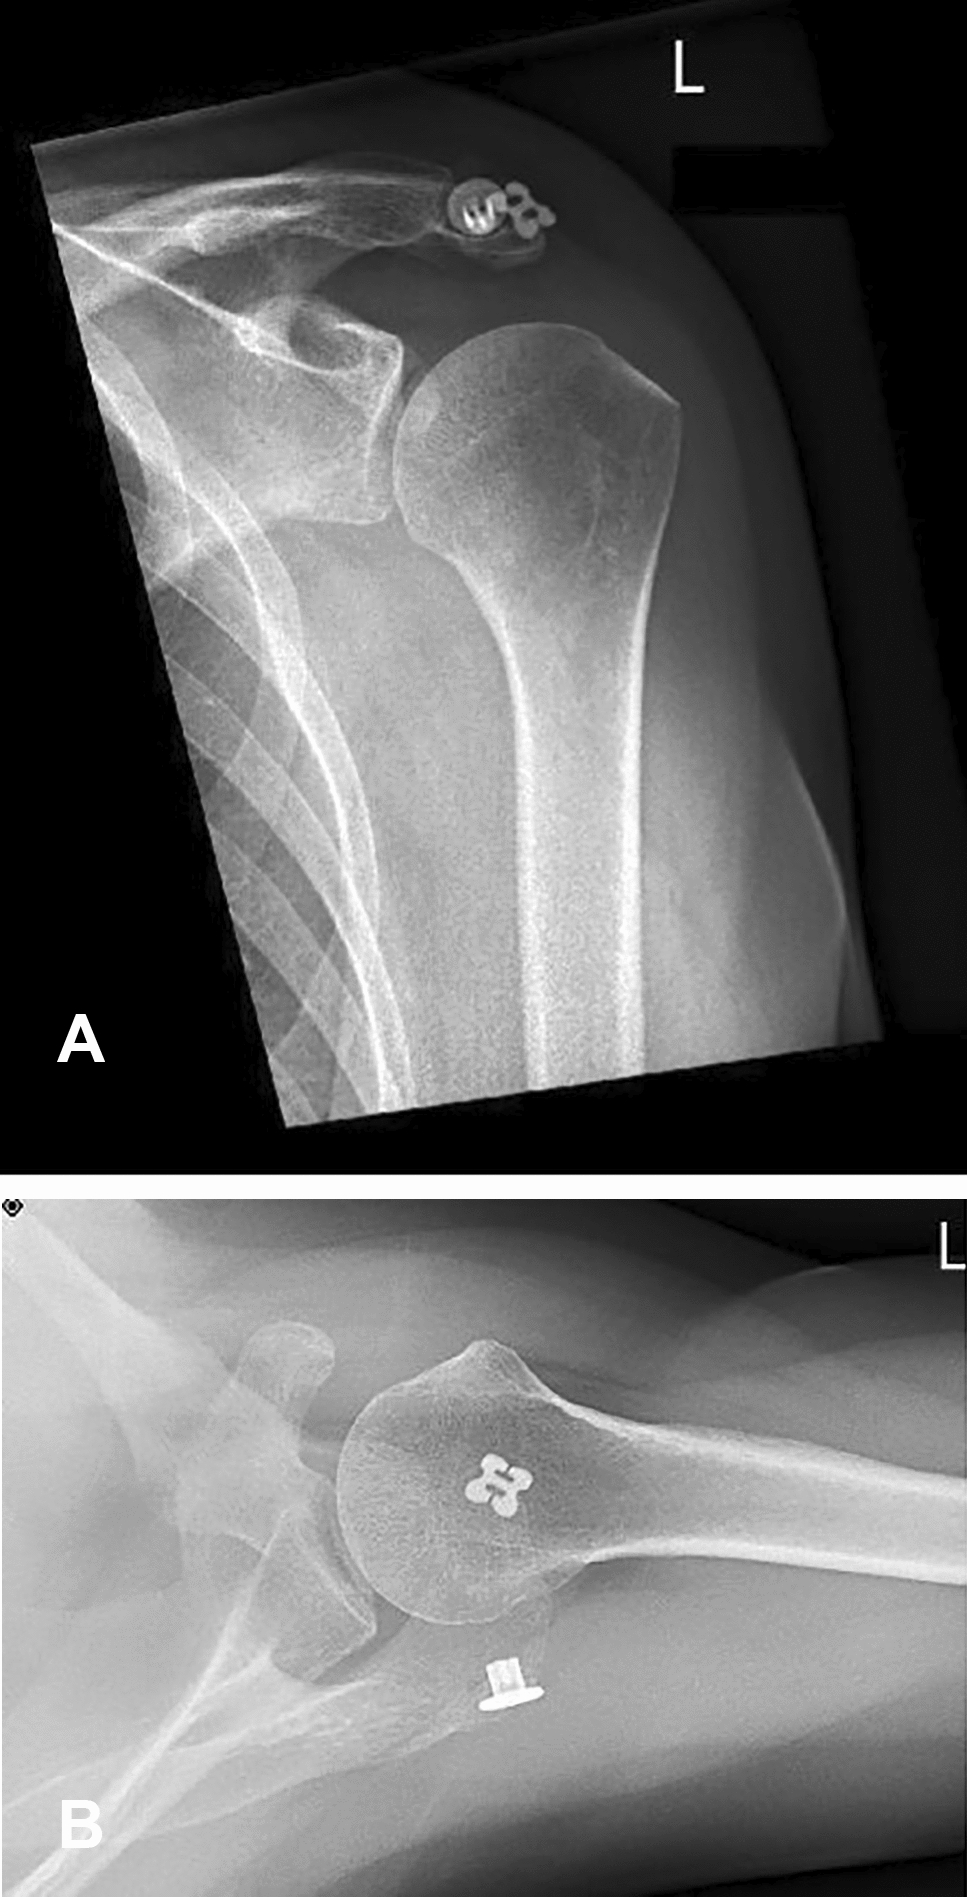

Postoperative rehabilitation involved initial shoulder immobilization in a Donjoy® Ultrasling® (DJO Global) for 8 weeks accompanied by physiotherapy and analgesia. One year after surgery, the persisting consolidation of the os acromiale and the proper position of the implant were confirmed by radiographs and computer tomography imaging (Figs. 4 and 5). The patient remained pain free and the hardware was not palpable. No noticeable discomfort around the implants was experienced. The assessment of the subjective shoulder value (SSV) showed 90%. The shoulder range of motion improved to 180° flexion, 170° abduction and 50° external rotation.

Fig. 4

AB Anteroposterior and axillary view radiographs at the 12-month follow-up